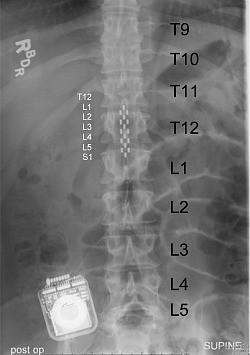

Epidural electrical stimulation involves implanting an electrode array along the lower part of the spinal cord, which ordinarily controls movement of the hips, knees, ankles and toes. Unlike similar approaches, the electrodes aren’t being used to directly stimulate the muscles. Instead, they act to reengage the spinal cord’s local nerve network, which doesn’t require input from the brain to carry out basic motor functions. The researchers surmised that this stimulation, combined with sensory input such as stepping on a treadmill could lead to movement.

In the latest study four candidates were chosen, Kent Stephenson, Andrew Meas and Dustin Shillcox. All four had experienced their spinal cord injuries at least two years prior to the study, and two of them were considered to have no chance of recovery.